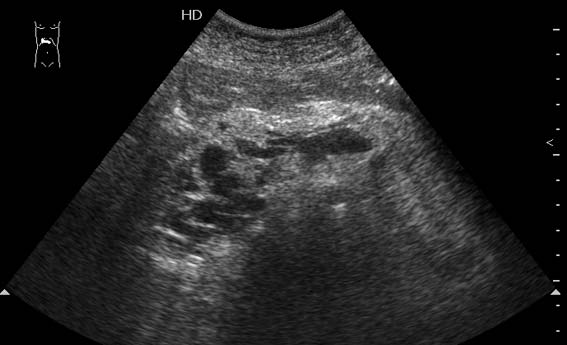

Тромбоз верхней брыжеечной вены

Женщина средних лет, клинический диагноз при поступлении - хронический панкреатит

Ваше заключение?

Я думаю, что все-таки тромбоз селезеночной вены

Верхней брыжеечной

Да, действительно, формирование варикоза в области головки панкреас характерно для тромбоза верхней брыжеечной вены.Брехт писал(а):Верхней брыжеечной

Ургентность здесь относительная, это неострый тромбоз - для развития коллатералей необходимо время. В хирургической клинике при хроническом панкреатите мы нередко видим тромбозы воротной вены, селезеностой вены. Но тромбоз ВБВ встречается нечасто и заподозрить его можно по "гроздьям" варикозов в области головки панкреас. На пилетромбоз обычно указвают "гроздья" варикозов в воротах печени.besliu писал(а):Спасибо за случай,впервые вижу такую патологию,ургентность в поликлинике не так уж частая![]()